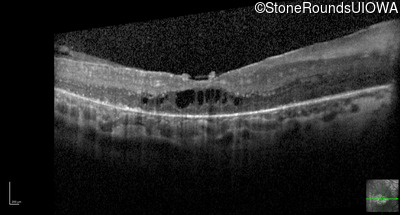

Optical Coherence Tomography - Left - 20/80 -1

Exemplar / OCT Stack

OCT Stack